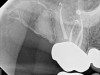

Fig 2. Tooth No. 14 was treated with silver points. In Figure 2, tooth No. 18 with mesial canals treated with Sargenti paste. The hallmark radiographic appearance of this technique is the light radiopacity within the canal system, as in Figure 3.

Figure 2

No obturation material nor method for placement available today is truly ideal. Though the dental manufacturing industry periodically introduces new materials with promise, many have been abandoned given major deficiencies in their efficacy or safety.  For example, silver points were once well accepted as root filling materials, but were abandoned decades ago due to moisture-related corrosion creating leakage and staining.4 Additionally, silver points proved especially difficult to remove during orthograde retreatment procedures due to the corrosion (Figure 2). Other historic techniques, like the now infamous paraformaldehyde-based Sargenti Method, proved dangerous due to toxicity to the adjacent periapical and surrounding tissues5 (Figure 3). More recently, the technique of complete bioceramic cement obturation has been developed. Though useful with open apices for apexification or in repairing other root deficiencies such as strip perforations, its inability to be removed readily from the root canal system means it should be reserved for those cases lacking suitable alternatives.6